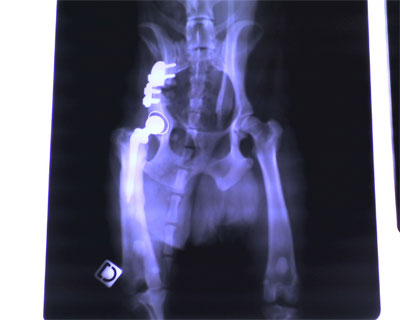

Pendant les vacances de février 2005,

mon chemin croisa un méchant Rottweiller qui me sauta dessus en

me faisant très mal à la patte. Pour redevenir un petit

chien presque normal j'ai du subir 5 opérations et la pose d'une

prothèse de la hanche ainsi que d'une plaque et des vis

pour maintenir mon bassin que l'on a été obligé de

me coupé et le basculer pour empecher la prothèse

de se déboiter. Maintenant j'arrive à plier ma

patte quasiment normalement, mais il a fallu attendre plus d'un an.